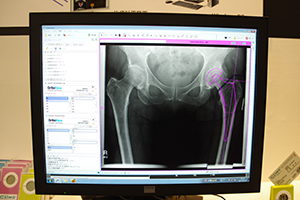

●OrthoViewによる整形外科の手術プランニングを提案

前回のITEMでも展示されていた整形外科向けのプランニングソフトウエアであるOrthoViewのデモンストレーションが行われた。従来,整形外科領域の人工関節置換術などでは,術前に行う角度や長さの計測をフィルム上で行っていたが。医療機関内でのPACSの導入が進んだことによって,システム上で処理したいというニーズが高まっている。OrthoViewは全世界で2000施設以上に採用されているソフトウエアであり,簡単な操作で整形外科領域の術前プランニングが可能である。独自のウィザード機能により,角度の計測やインプラントの位置合わせなどの処理が,項目を選択していくだけで自動的に行えるようになる。人工股関節全置換術用のウィザード“Smart Hip”を使用した場合,60秒以内にプランニングが完了する。

ソフトウエア内に収録されているインプラントの種類は1万5000以上であり,ユーザーの要望に応じて追加していくという。